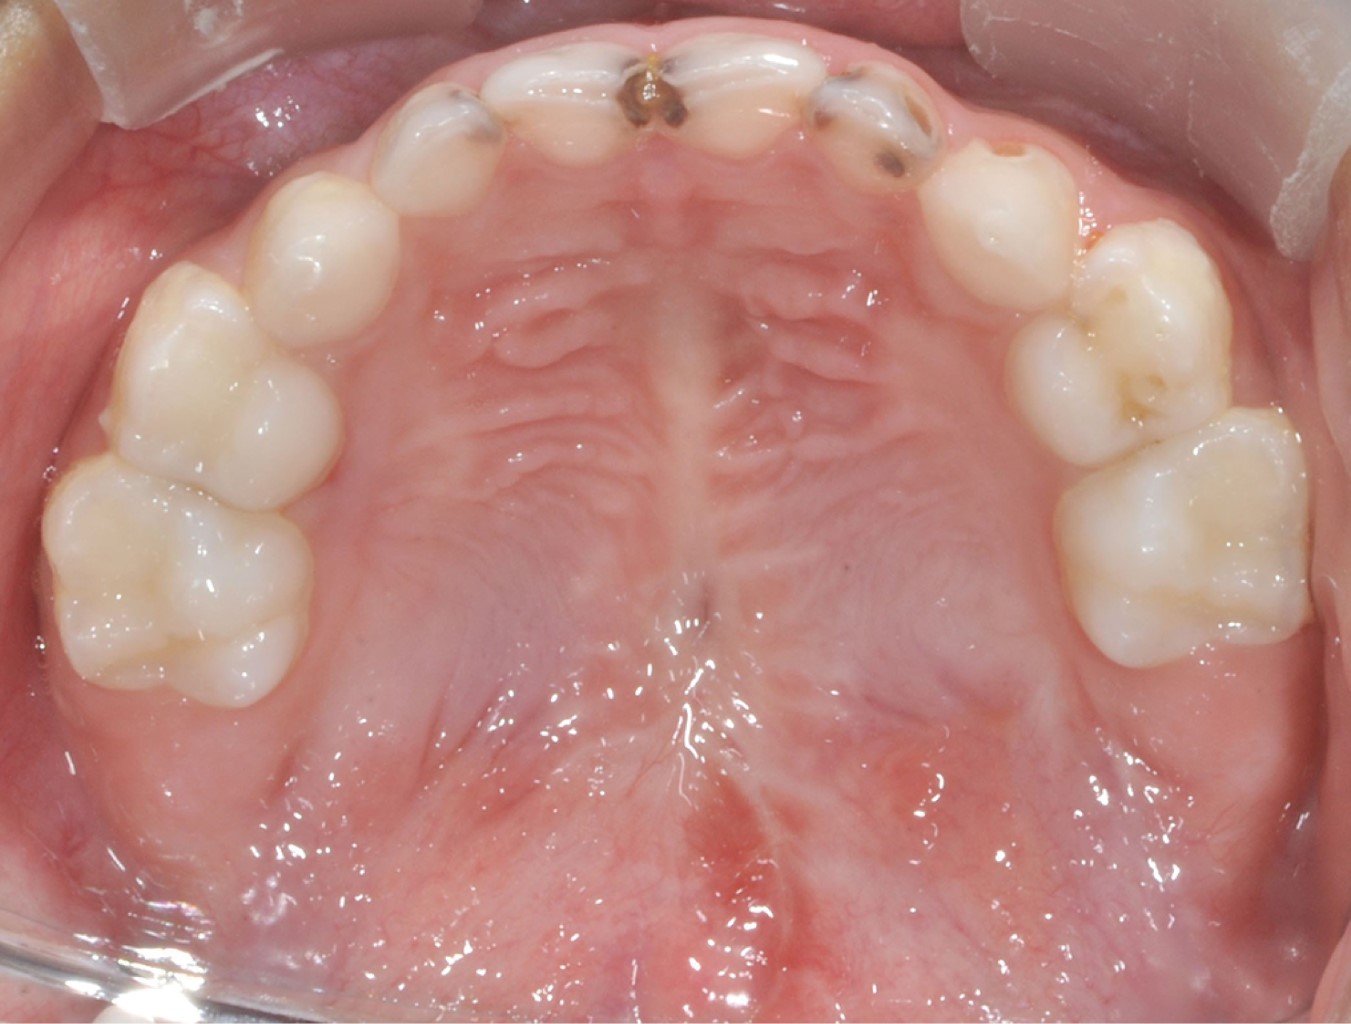

Después de seis meses de la palatoplastia primaria, se decidió realizar cierre de fístula. Con el paciente bajo anestesia general balanceada, se efectuaron incisiones en los bordes de la fístula, separando las capas nasal y oral, cerrando en dos planos, utilizando un colgajo de mucosa oral invertida para la capa nasal y reclutando tejidos locales para un colgajo mucoperióstico utilizado para el cierre de la capa oral, apoyado de incisiones relajantes. El procedimiento se llevó a cabo sin complicaciones ni eventualidades (Figuras 4 y 5). El paciente fue dado de alta; acudió a controles postoperatorios después de una semana, un mes y seis meses, cursando con una cicatrización adecuada. Actualmente cuenta con dos años de evolución, se encuentra asintomático y sin datos de recidiva de fístula palatina (Figura 6).

Figura 6